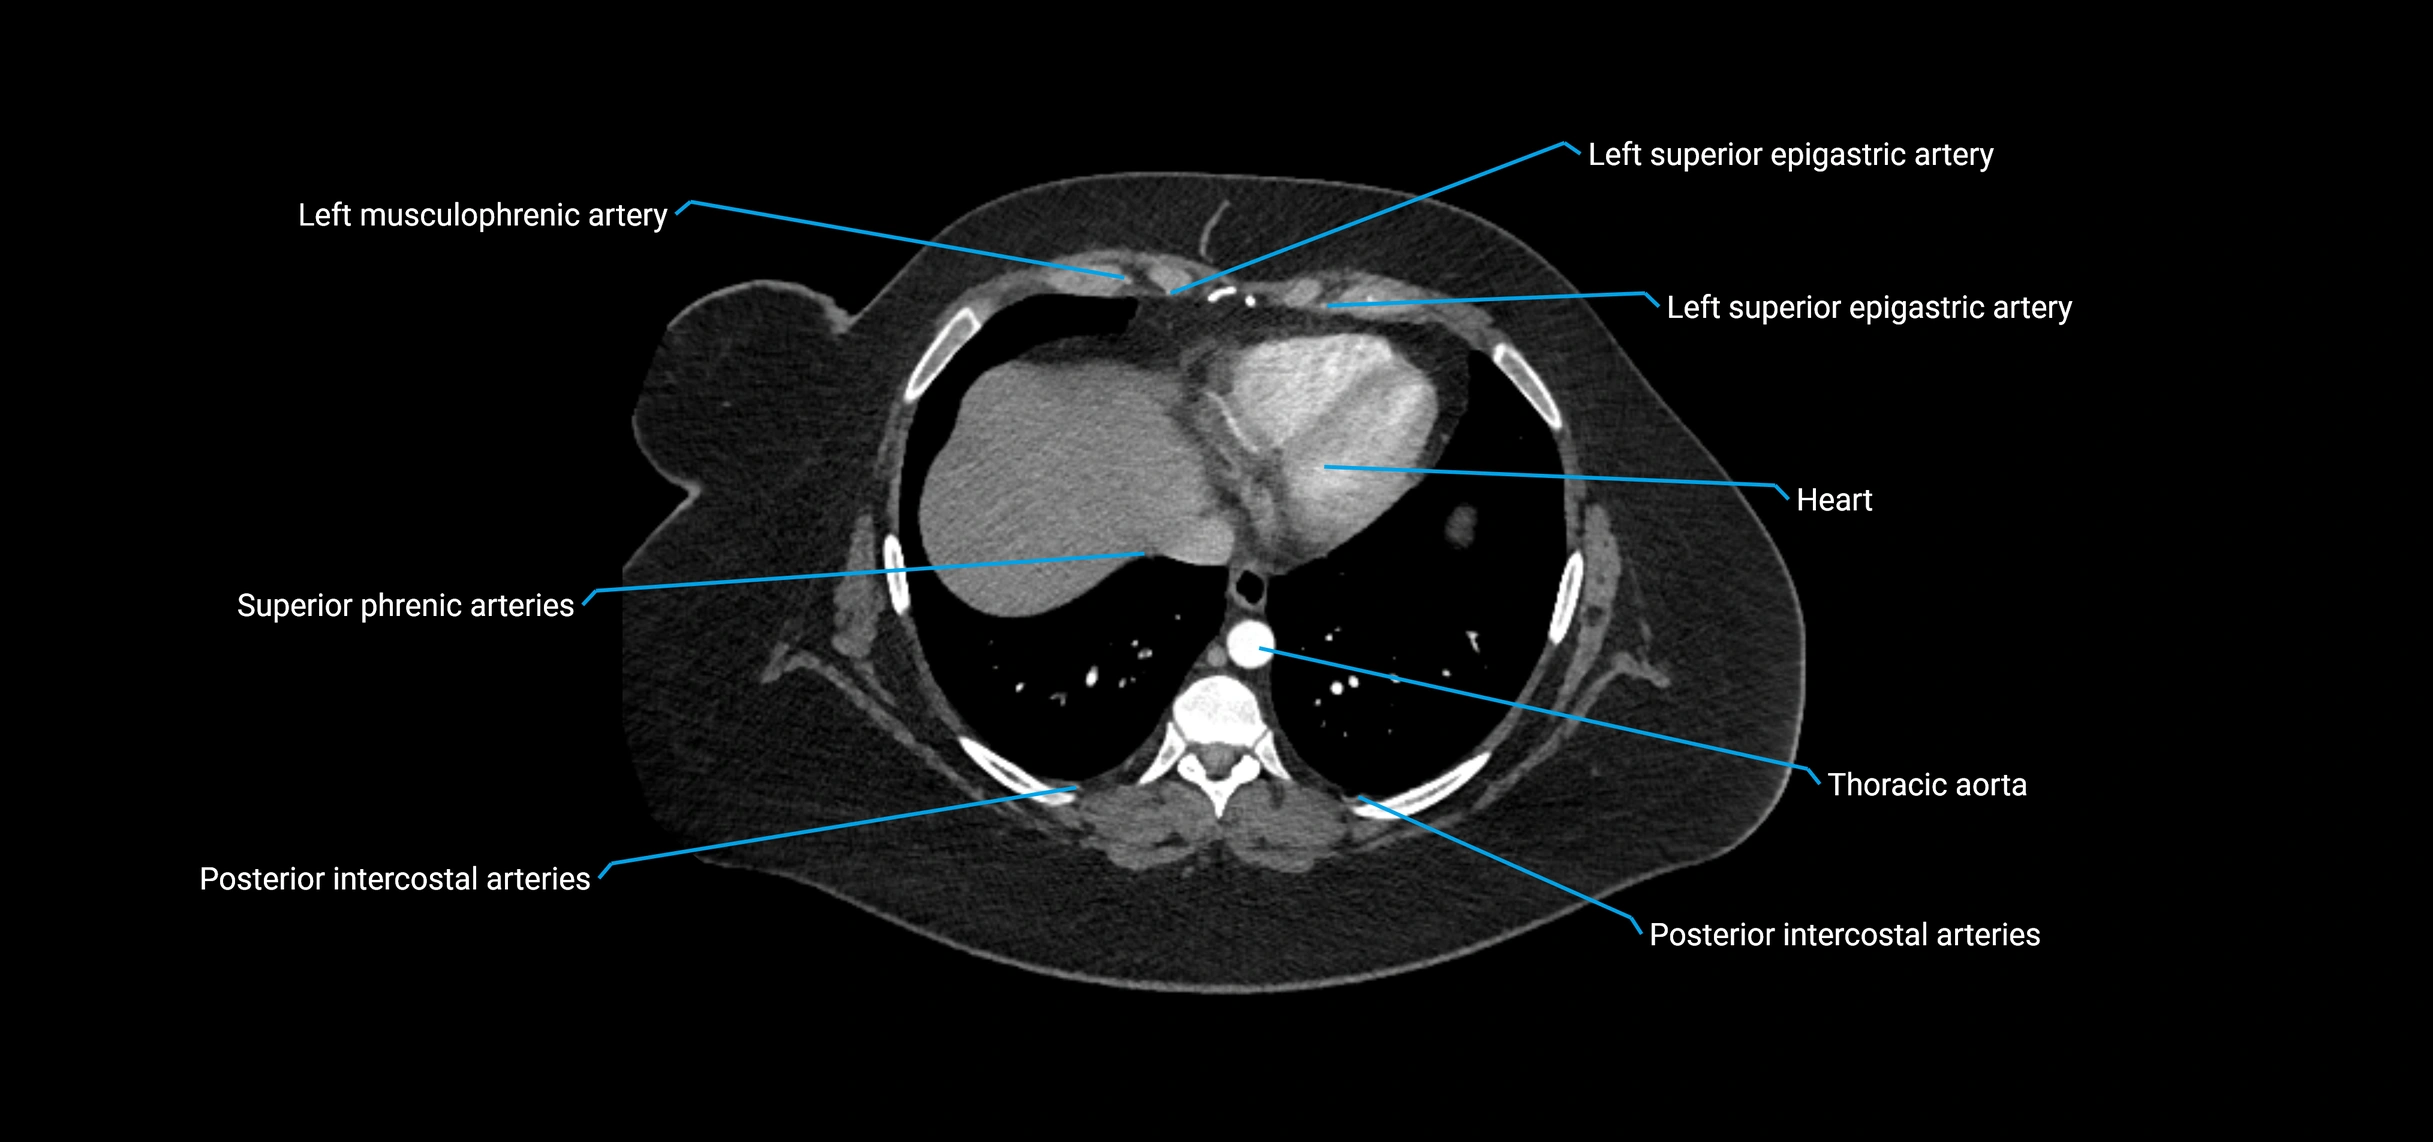

Contrast-enhanced CT (CTA):

• Gold standard for abdominal aortic imaging

• Provides excellent detail of lumen, wall, aneurysm, thrombus, and branch vessels

• Multiplanar and 3D reconstructions help in aneurysm measurement, stent graft planning, and dissection evaluation